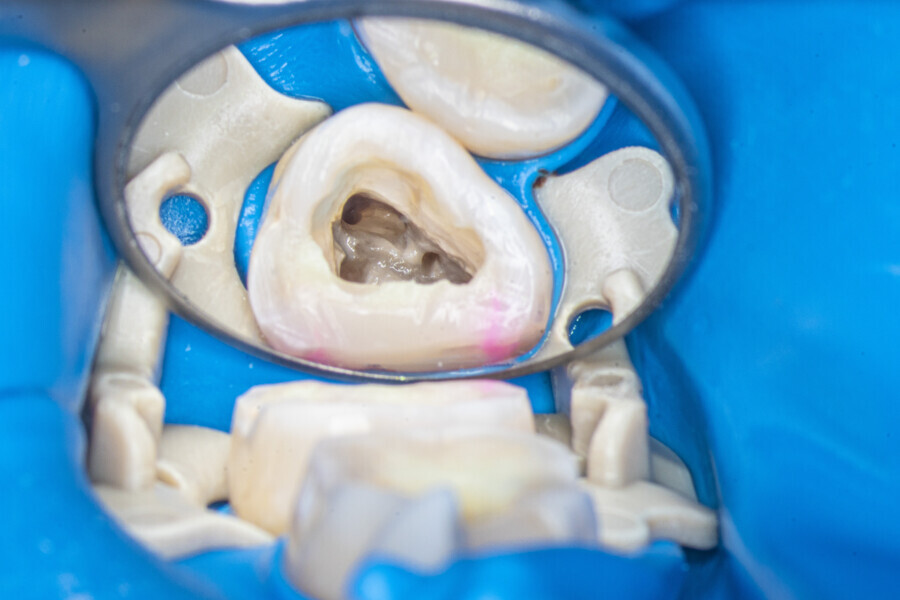

The first trials of the LPE concept were performed on extracted human molars. Although the dynamics of fluid during root canal irrigation are completely different in vivo than in extracted teeth, these kinds of trials provide initial information about the procedure. Some of these teeth had apices closed with a coat of wax and composite resin to close the apical delta and simulate the periapical tissue. After creation of the access cavity, the pulp chamber was cleaned with continuous irrigation with 5.25% NaClO activated with a SkyPulse laser (Fotona) in AutoSWEEPS mode (20 Hz, 15 mJ). A 25/0.07 reciprocating file (Shenzhen Perfect Medical Instruments) was used to perform the pre-flaring procedure. After opening the coronal third, continuous irrigation with 5.25% NaClO activated with the laser was used to clear the debris for 30 seconds. After removing the debris, a #10 C-PILOT file (VDW) was used to establish apical patency, without forcing the file if possible. In some cases, apical patency was reached already at this stage of root canal preparation. In all cases, the second step of instrumentation was the preparation of the middle third with the same file, and the same irrigation procedure was performed. Subsequently, the C-PILOT file was used to reach the apical foramen. At this stage, apical patency was reached in most cases, but in some roots, there was no possibility of entering the apical foramen. The working length was confirmed with a radiograph with the hand file. Usually, the next procedure to be done is apical preparation, but the LPE concept is based on an enhanced irrigation protocol. Following this protocol, irrigation was performed for 5 minutes with continuous flow of 5.25% NaClO activated with the SkyPulse laser in AutoSWEEPS mode (20 Hz, 20 mJ) with a conical sapphire fibre. The next step was alternating irrigation with 17% EDTA for 30 seconds, with 5.25% NaClO for 30 seconds and with 17% EDTA for 30 seconds, all activated with AutoSWEEPS, followed by irrigation for another 5 minutes with 5.25% NaClO activated with AutoSWEEPS. In most cases, the next step after this stage of enhanced irrigation was the calibration of the apical constriction rather than apical preparation per se, but this step requires further investigation.

A 30-year-old female patient presented to the office owing to pain related to the maxillary right first molar. The radiograph revealed a periapical radiolucency, indicating exacerbated chronic periapical periodontitis. The access cavity was created with the Safe Access and Preparation Concept burs set (manufacturer). The pulp chamber was cleaned with 5.25% NaClO activated with the SkyPulse laser. Four orifices were located, and all four canals were shaped in the same sequence described previously. The LPE enhanced irrigation was performed with activation by the SkyPulse laser. In the mesial root, a clean isthmus was visible, and the irrigants started to flow between the MB1 and MB2 canals in the apical third, which was confirmed with a micro-suction cannula. In the MB1, MB2 and DB canals, apical preparation was performed with Endostar E3 Azure files (Poldent) up to size 25/0.04 owing to the apical curvatures. In the DB canal, patency was not established. The final irrigation protocol was performed in the same sequence as described before. The periapical radiograph confirmed that the isthmus was filled with the sealer.

A 35-year-old female patient was referred to the office owing to the lack of patency in the pulp chamber. The periapical radiograph and CBCT image confirmed that the pulp chamber was completely calcified. The calcification of the pulp chamber was removed with diamond-coated ultrasonic tips. After removing the calcification, four orifices were located and shaped in the sequence described previously. The LPE enhanced irrigation protocol with the SkyPulse laser was performed. In this case, the MB2 canal joined the MB1 canal approximately 4 mm before the apex and was shaped only to this length. Apical preparation and irrigation were performed as described previously. The periapical radiograph revealed that the MB2 canal had a separate apical part, which was cleaned with the irrigants and filled with the sealer, and that the palatal canal had two portals of exit.